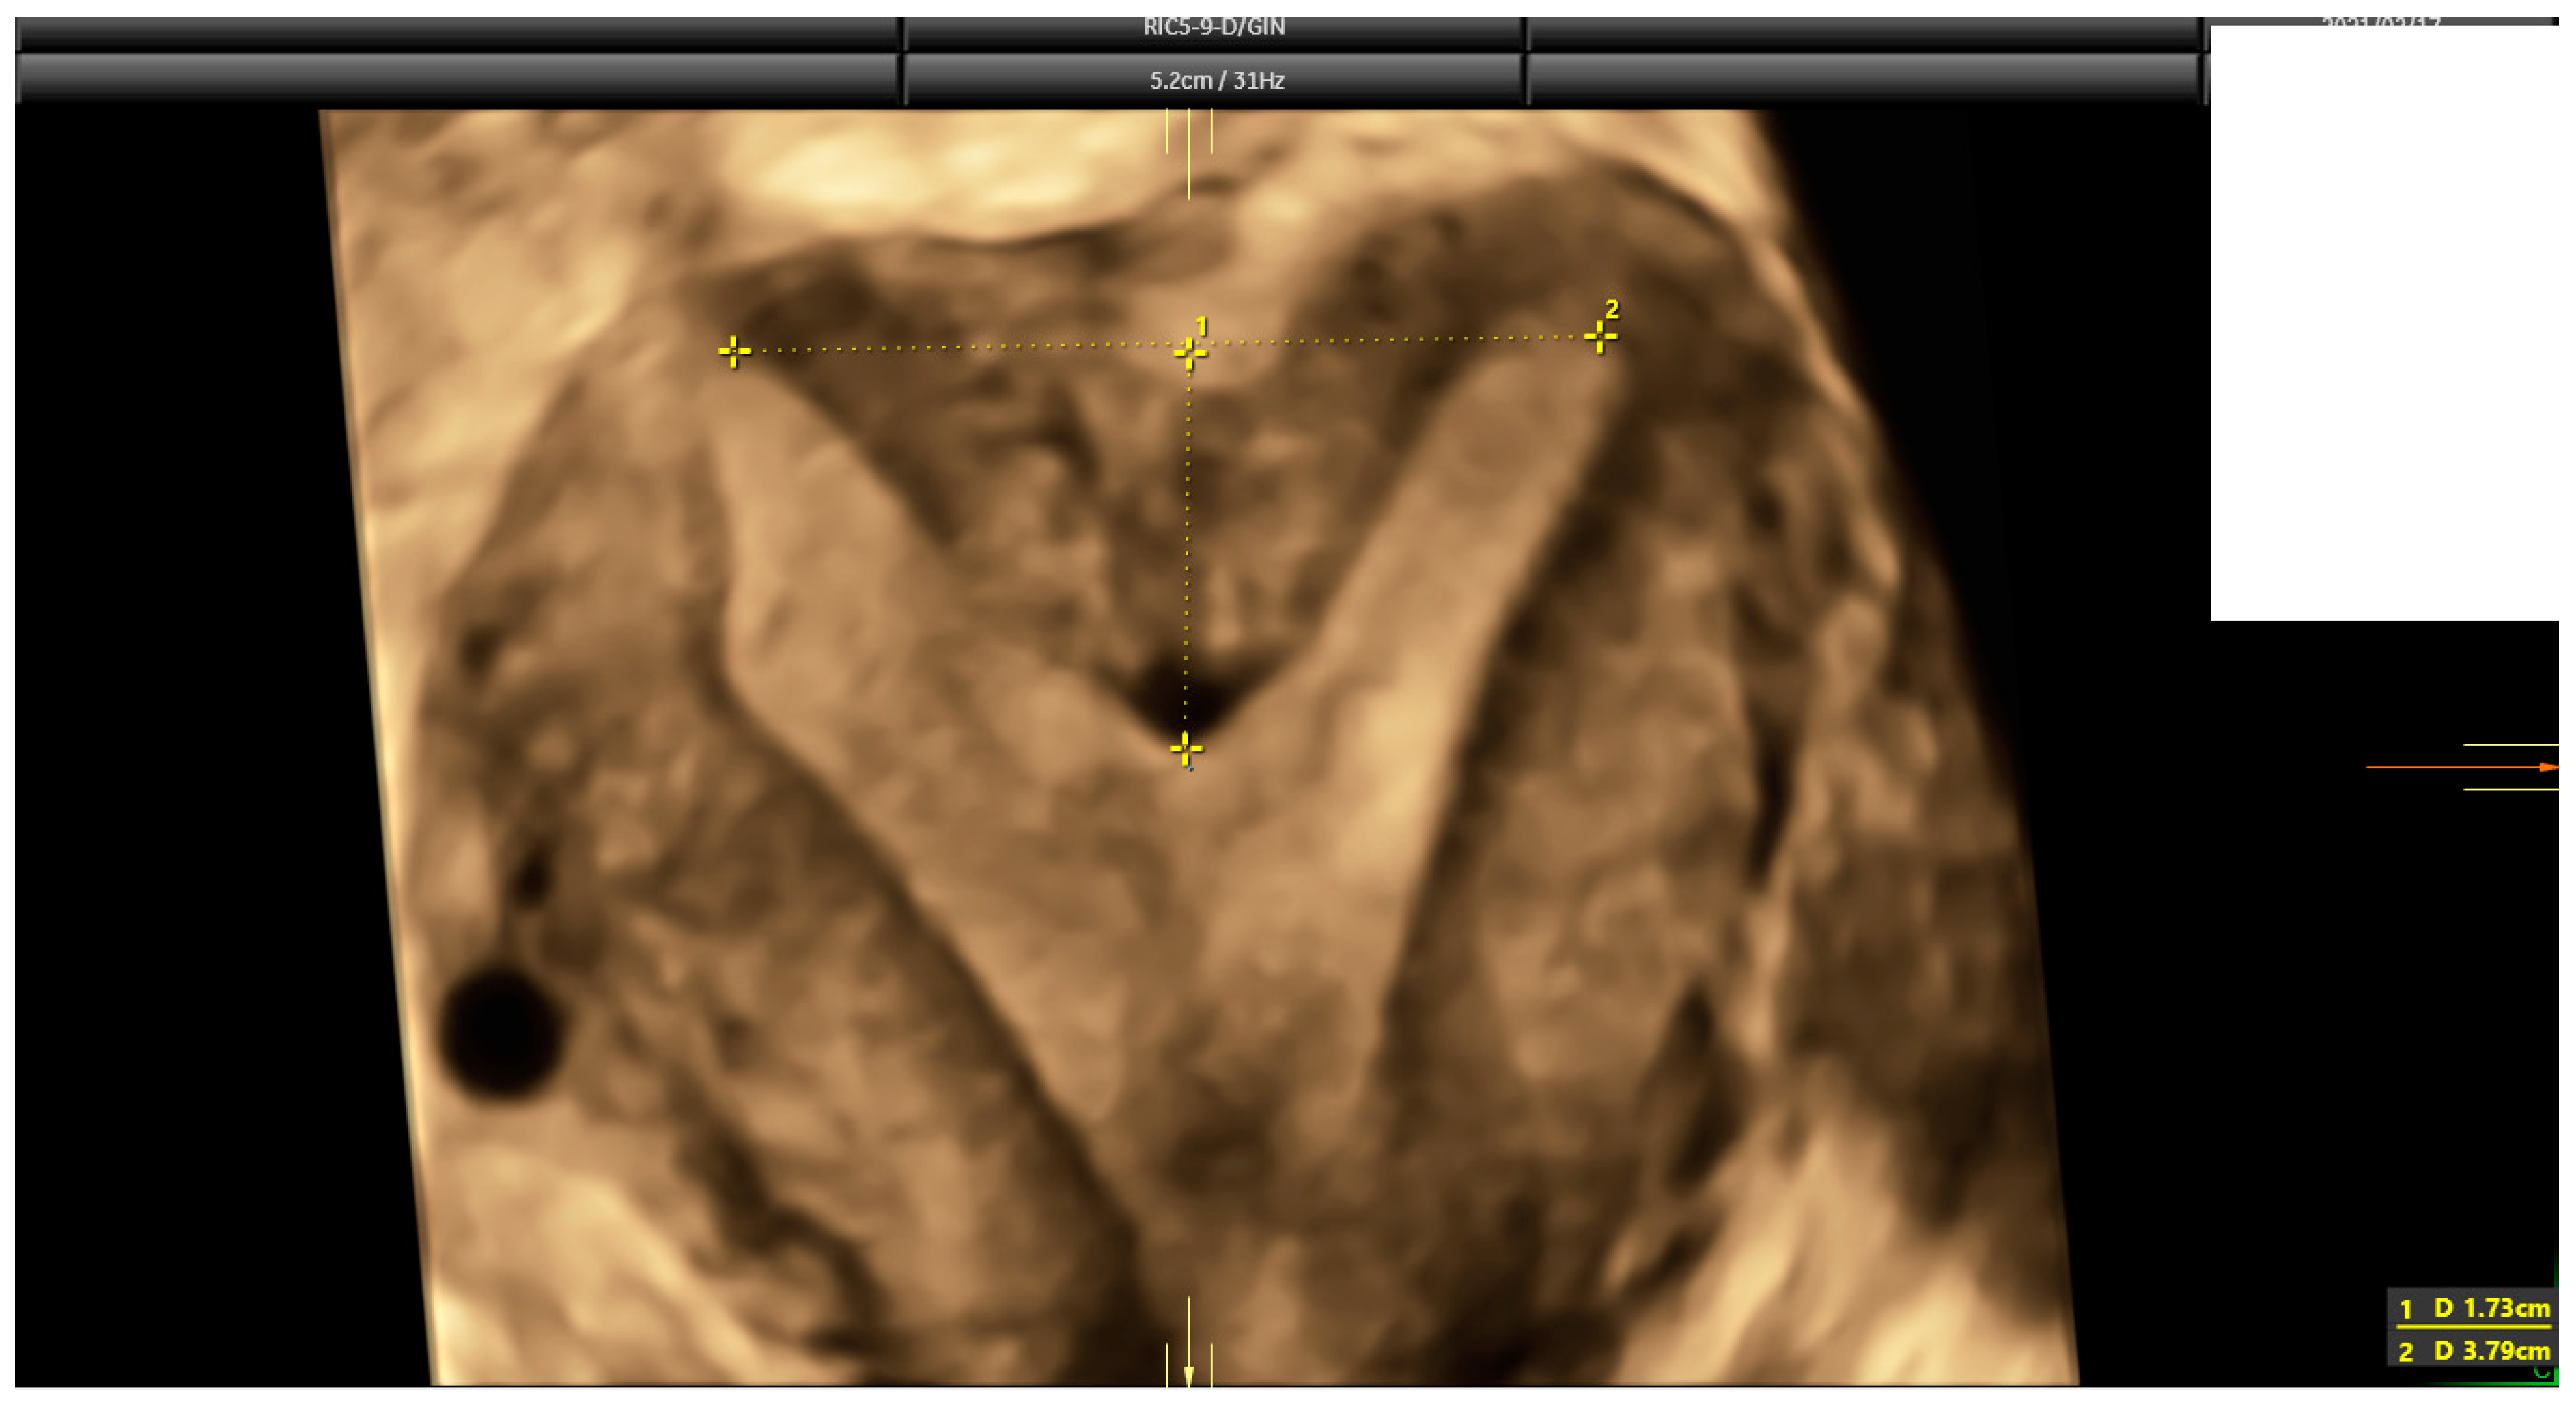

The diagnosis of a septate uterus was determined according to four different criteria (2016-ESHRE-ESGE, 2016-ASRM, 2021-ASRM, and 2019-CUME) [9,12,16] (Figure 2, Figure 3 and Figure 4). The 2016-ASRM classification defines a septate uterus as having a uterine cavity indentation depth >15 mm and an indentation angle <90° [9]. The 2021-ASRM criteria define a septate uterus as having a cavity indentation >10 mm and an indentation angle <90° [10]. The ESHRE-ESGE classification identifies a septate uterus based on an indentation-to-wall-thickness (I:WT) ratio >50% with an external fundal indentation <50% [12]. The CUME criteria specify an indentation in the fundal cavity >10 mm with an external serosal indentation <10 mm [16].

Figure 3.

The same case as Figure 2. According to 2016 and 2021 ASRM criteria, this is a case that falls within the grey zone. Indentation length is 17.3 mm, but indentation angle is 104° (larger than 90°).